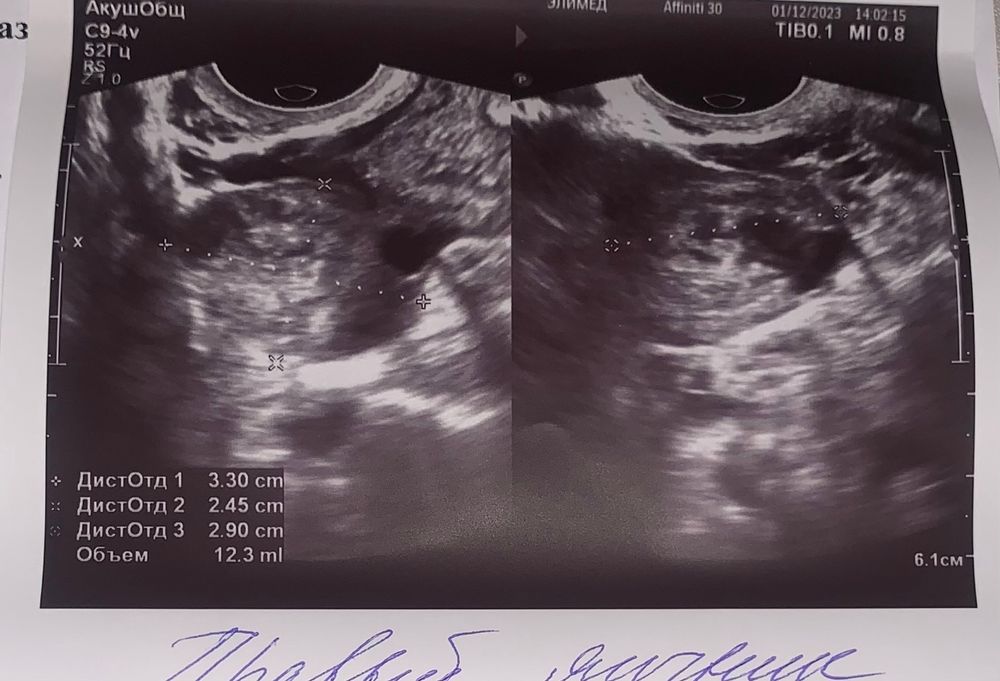

постовуляторный фолликул….Какой врач это писал.Хрен пойти что он имел ввиду то ли желтое тело,то ли доминантный фолликул.

Элис , и если это желтое тело,оно маленькое 12мм всего.Вам надо сдать прогик на 5-7дпо чтобы посмотреть хватит ли прогестерона для прикрепления и далее.